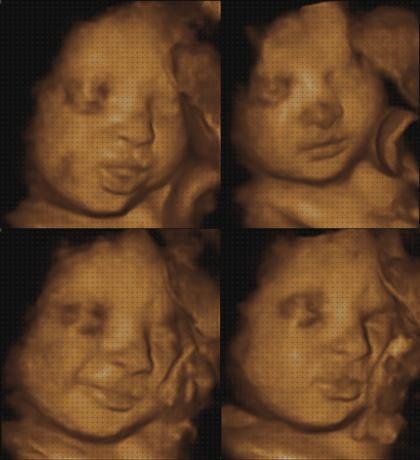

Para la ecografía del primer trimestre, el profesional de la sanidad está moviendo un aparato de ultrasonido sobre el abdomen. El gadget hace uso de ondas sonoras para explorar al feto. El profesional de la robustez observará el grosor de la parte posterior del cervical del feto, que es una marca del manifestación de down.